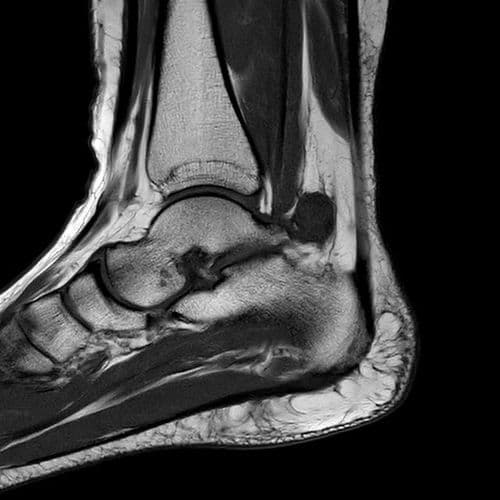

Douleur non traumatique latérale à la cheville, exacerbée par l'activité physique.

US